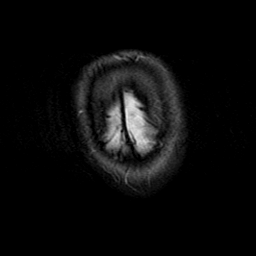

Subacute Stroke, overlay -- Slice #25

[Home][Help][Clinical] Slice 25